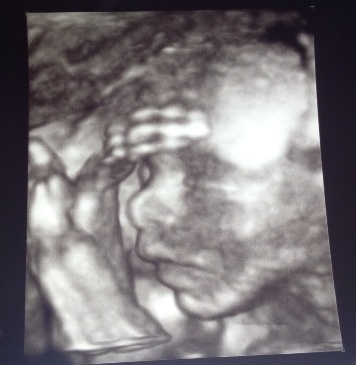

So they say its easier to pip on mobile now...here goes nothing. Here's a pic of my rainbow baby at 30 weeks. She will be here in 2 more weeks! Feel free to share your us Aww pics here.